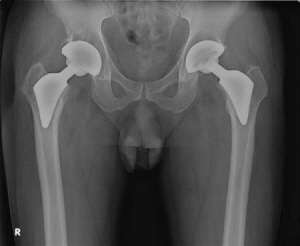

이대목동병원 인공관절센터 김영후 소장이 개발한 인공관절 ‘프록시마’ |

기존 일반적으로 사용되어 온 대퇴골두 인공관절 |

프록시마는 기존 인공관절보다 크기를 줄이는 대신 인체의 하중을 받는 대퇴부의 끝 부분에만 골 접착제 없이 삽입하는 인체공학적 디자인으로 설계돼 정상적인 뼈의 힘을 받는 부분에만 응력이 발생하도록 해줌으로써 뼈를 원래대로 보존해줘 오랫동안 사용할 수 있다. 기존에 일반적으로 사용되던 모양이 긴 엉덩이 인공관절은 고정력을 높이기 위해 길이가 긴 아랫 부분을 인체의 뼈에 깊숙이 삽입하므로 수술 후 대퇴부에 통증이 올 수 있고, 오랫동안 사용하다 보면 주위 뼈 조직이 약해질 수 있어 재수술을 받아야 하는 단점이 있었다.

프록시마는 세라믹 델타 소재를 사용해 강도를 2배로 늘리고 마모도는 기존 소재 대비 1/5000로 대폭 줄여 인체에 미치는 부작용을 최소화했다. 또한 관절을 연결하는 볼의 크기를 36mm로 크게 해 탈구를 예방해준다. 기존의 대퇴골두 인공관절은 작은 크기의 볼을 사용해 탈구가 일어나는 일이 있곤 했다.